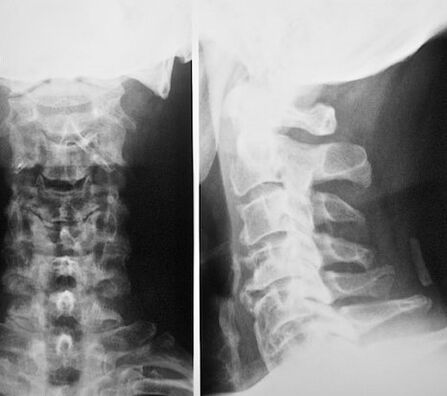

هشاشة عظمي عنق الرحم هو مرض تدريجي يتميز بالتغيرات غير التنكسية في الأقراص الفقرية ، التي يتم تسليم التشوهات إليها ، وتغيير بنيتها ، والتي تسبب عدد من الأعراض الواضحة. إن الخطر على تطور هشاشة العظم في منطقة عنق الرحم هم أشخاص لديهم نمط حياة جالس أو الذين تم ربط نشاطهم المهني منذ فترة طويلة بالجسم في وضع ما. فيما يتعلق بحدوث هشاشة العظم ، فإن الأضرار التي لحقت العمود الفقري عنق الرحم في المركز الثاني بعد هشاشة العظم القطني. إن خصوصية المرض وتعقيده هو أن آفة منطقة عنق الرحم تؤثر دائمًا على جذور الأعصاب للأعصاب الفقرية والأقراص الفقرية للعمود الفقري ، مع هزيمة الأوعية الكبيرة والصغيرة من قبل إمدادات الدم إلى الدماغ.

تحتوي مقصورة عنق الرحم على بنية معقدة وتتكون من 7 فقرات ، كل منها يؤدي عددًا من الوظائف: يدعم الرأس ، المنعطفات ، ينحني الرقبة وغيرها من الوظائف المهمة. هناك بين الفقرات التي تجعل العمود الفقري مرنًا ودائمًا ، والأقراص الفقرية نفسها تتكون من حلقات ليفية توجد فيها تناسق. تتناسب فقرات عنق الرحم القريبة من بعضها البعض ، وهذا هو السبب في أن النشاط البدني الطفيف يمكن أن يتسبب في تحولها ، مما يعني بدوره أن الأوعية الدموية والأعصاب يتم الضغط عليها. في العمود الفقري عنق الرحم ، توجد الشرايين الفقرية المسؤولة عن إمدادات دم الدماغ. إذا كان يضغط عليه ، فإن إمدادات الدم منزعج ، لا يتلقى الدماغ مواد مهمة بما فيه الكفاية ، مما يؤدي بلا شك إلى هزيمته وتطور سلسلة من المضاعفات ، مما قد يؤدي إلى إعاقة المريض أو حتى الموت.

على الرغم من انتشار هذا المرض والأداء في الطب الحديث ، لم يتم فحص التسبب في هشاشة العظم في العمود الفقري عنق الرحم بالكامل. من المعروف أن المرض يمكن أن يتطور على خلفية عمليات الضعف الأيضية في العمود الفقري عنق الرحم ، مما يؤدي إلى تغيير في بنية الأقراص الفقرية والجسم الفقري مع مرور الوقت. من بين أنواع أخرى من هشاشة العظم ، تعتبر عنق الرحم الأكثر خطورة ، حيث يتم ضغط جذور الحبل الشوكي والأوعية الدموية أثناء تطوره ، مما يؤدي بلا شك إلى انتهاك لإمدادات الدم بخلايا الدماغ. في التسبب في المرض ، يميز الأطباء العديد من العوامل الاستفزازية التي يمكن أن تؤدي إلى تطور المرض.